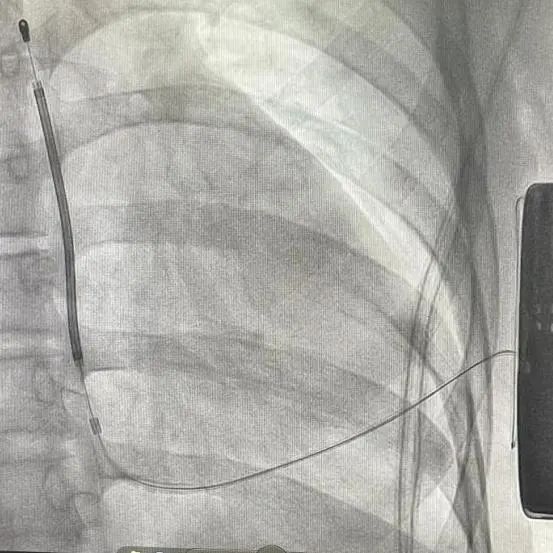

手术在全麻醉下进行。常规消毒、铺巾,取左腋中线平等第5-6肋为预定点,切开一约7cm切口,逐层将皮下组织分离直至肌层,在前锯肌与背阔肌之间寻找到深筋膜层,以确保囊袋在患者的脂肪层下并且足够容纳装置。

再次于胸骨柄右缘1cm为预定点,切开一长约4cm切口,逐层分离至深筋膜层,预埋两根缝合线用导引针,于切口间建立隧道,利用隧道针将电极沿皮下置入囊袋。再以切口位置建立隧道,同样以隧道针将导线头端沿深筋膜层,送至胸骨柄上缘(距切口14cm处,于切口处固定电极导线,囊袋处连接脉冲发生器(S-ICD A209),固定脉冲发生器于深筋膜层。

排除空气后关闭深筋膜层,进行DFT测试。两位患者均采用50HZ,200MA交流电方式进行诱颤,SICD均正确识别且65J除颤一次成功,除颤阻抗分别为85欧姆和59欧姆。缝合皮肤,术区纱布覆盖,包扎,弹力绷带加压包扎止血。手术圆满成功。第一台手术耗时2小时,第二台手术仅耗时1个半小时。

患者一:

患者二: